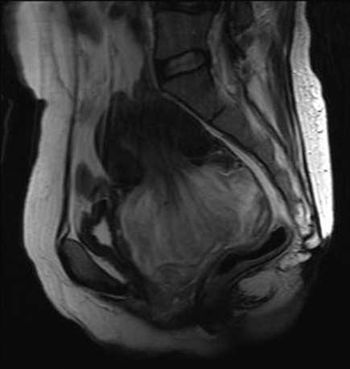

Clinical History: A 48-year-old female presented with vaginal bleeding, urinary frequency and lower abdominal pain.